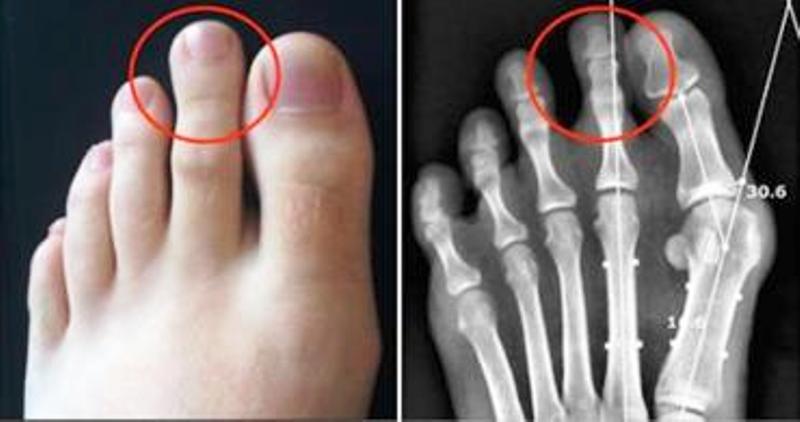

ماذا تعني "القدم اليونانية"؟

هذه القدم تتميز عن باقي الأقدام، كون الأصبع الثاني هو أطول من أصابع القدم الأخرى، كما يتصف أصحاب هذا القدم، بالشخصية القوية والجاذبية والذكاء.

يعتقد البعض أن هذه الظاهرة مجرد فروق جسدية لا تعني شيئاً، إلا أن من يمتلك "القدم اليونانية" يعاني من آلام فغالبا ما ينحني أصبعه عند الجري أو المشي، ويسبب له آلاما والتهابات، لذلك ينصح بارتداء الاحذية المريحة المناسبة لحجم قدمك مع مراعاة ان يكون متسعا للاصبع الكبير، وفقاً لما اورده موقع لبنان 24.